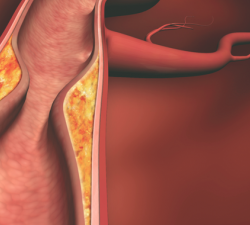

Atherosclerotic cardiovascular disease (ASCVD) is the leading cause of mortality and morbidity in United States.

Sarika Desai, DO

A man with a history of obesity, hypertension, and hyperlipidemia presented to the clinic with intermittent chest tightness upon exertion.